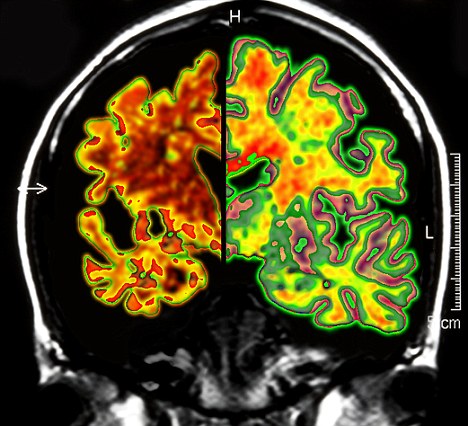

其實早在2010年,加拿大就已經(jīng)對這種大腦“起搏器”展開臨床試驗。當(dāng)時,有6名輕微老年癡呆癥患者參加。當(dāng)時的試驗結(jié)果顯示,在13個月的觀察期中,這些病患的葡糖糖代謝速度持續(xù)上升,這也就說明他們的大腦神經(jīng)元正在工作。而在同時期內(nèi),大部分老年癡呆癥患者的葡萄糖代謝水平則是在不斷下降。